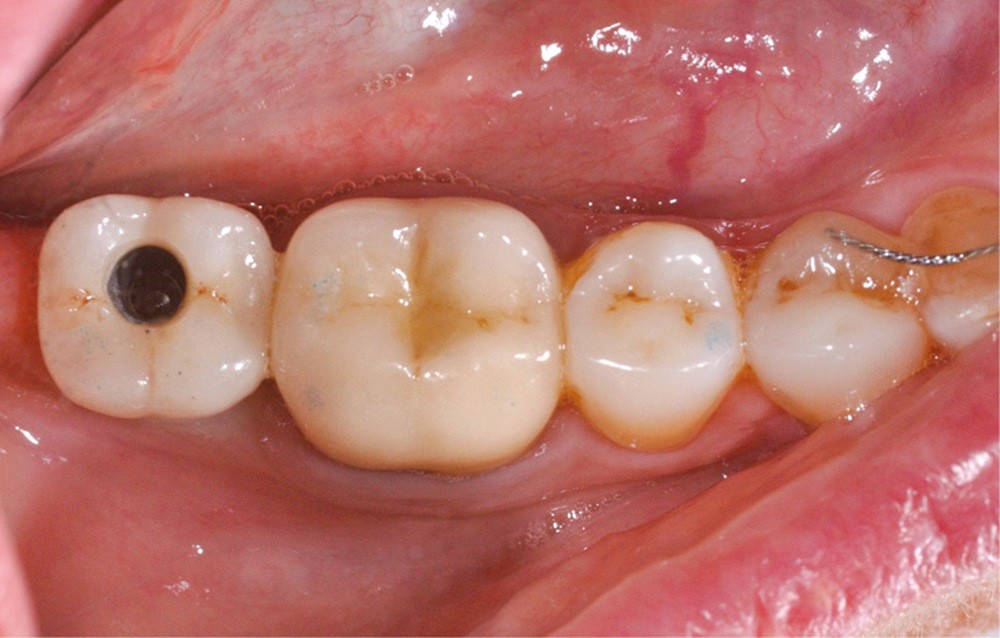

Au moment du scellement, la suprastructure est remplie du matériau d’assemblage, puis positionnée entièrement, mais sans pression, sur ce duplicata, et immédiatement retirée pour être positionnée sur le pilier implantaire en bouche (fig. 4).